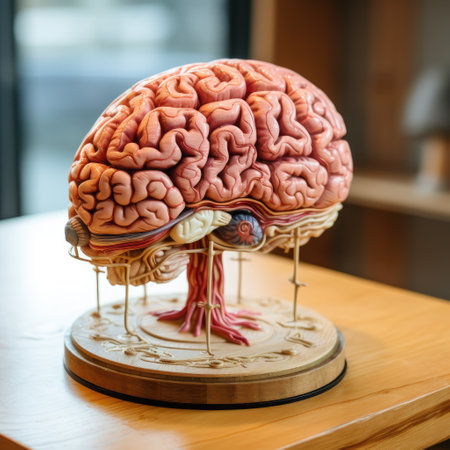

This detailed model showcases human brain anatomy, perfect for educational purposes. Ideal for classrooms, medical training, and scientific research.

This image showcases a detailed model of the human brain, highlighting its unique anatomy. The brain model is displayed on a rustic wooden surface, ideal for educational and scientific use.